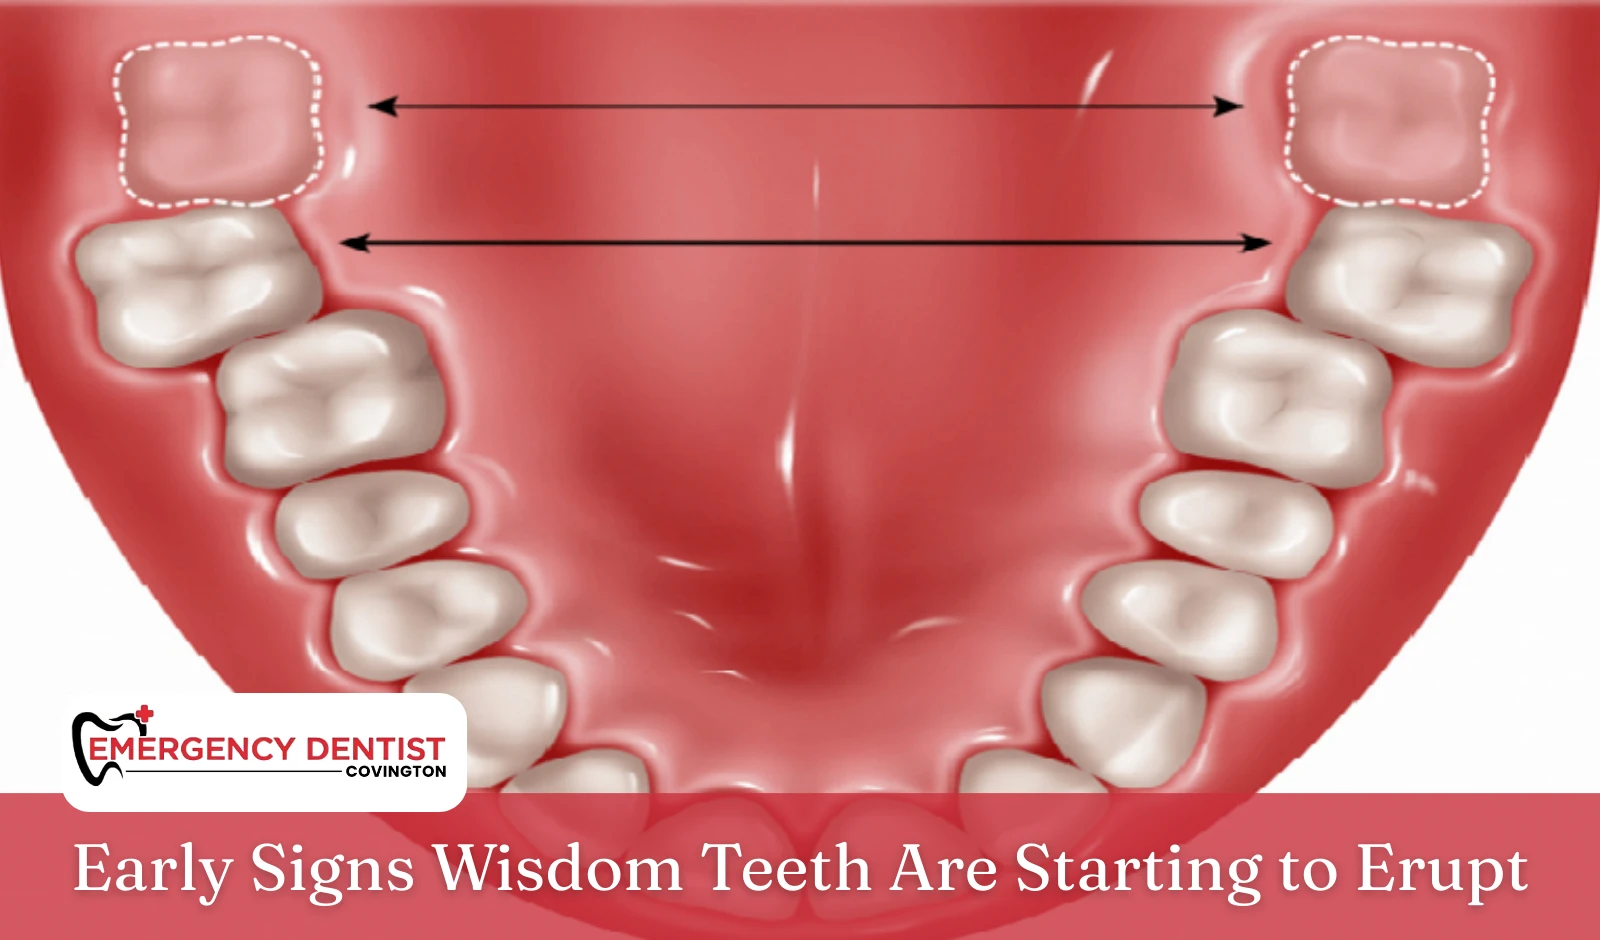

When Do Wisdom Teeth Come In?

One of the most common questions patients ask is when do wisdom teeth come in. For many people, wisdom teeth erupt sometime between the ages of 17 and the early twenties. That said, everyone’s timeline is different.

Because wisdom teeth develop after the rest of the mouth is already full, there may not be enough space. This can cause wisdom teeth to erupt slowly, grow at an angle, or remain partially emerged instead of fully breaking through the gum.

Impacted Wisdom Teeth Explained

- Impacted wisdom teeth remain trapped under the gum or jawbone

- An impacted wisdom tooth may press against nearby teeth

- Partially emerged teeth can trap food and bacteria

Over time, impacted wisdom teeth can increase the risk of gum disease and tooth decay, which may affect overall oral health if left unmonitored.